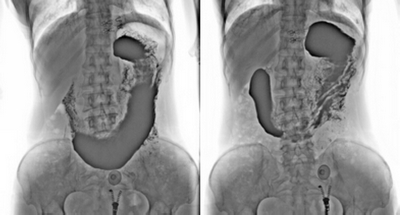

3. 數(shù)字化胃腸:

★消除普通數(shù)字胃腸機視野小的缺陷,直接獲得大視野全數(shù)字化圖像 (17x17) 。

★更加方便胃腸、食管、上消化道、全消化道等造影功能!